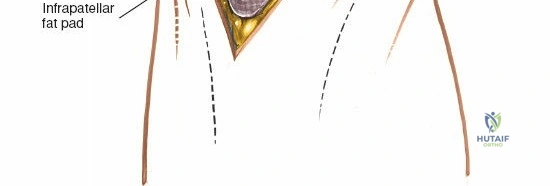

Deep to the extensor mechanism lies the joint capsule, which is continuous with the periosteum of the distal femur and proximal tibia. The capsule forms the suprapatellar pouch proximally, a crucial area for exposure and débridement. The synovial membrane lines the inner surface of the capsule and extends into the joint, forming the intra-articular fat pad (Hoffa's fat pad) distal to the patella.

- With the patella everted, the suprapatellar pouch is accessible. This is often adherent in osteoarthritic knees and requires sharp dissection to release adhesions and fully visualize the distal femur.

- The fat pad (Hoffa's fat pad) lies anterior to the intercondylar notch. It may be partially resected if it obstructs visualization, though excessive resection can contribute to anterior knee pain.

- Retractors are strategically placed to maintain exposure of the femoral condyles, tibial plateau, menisci, and cruciate ligaments.